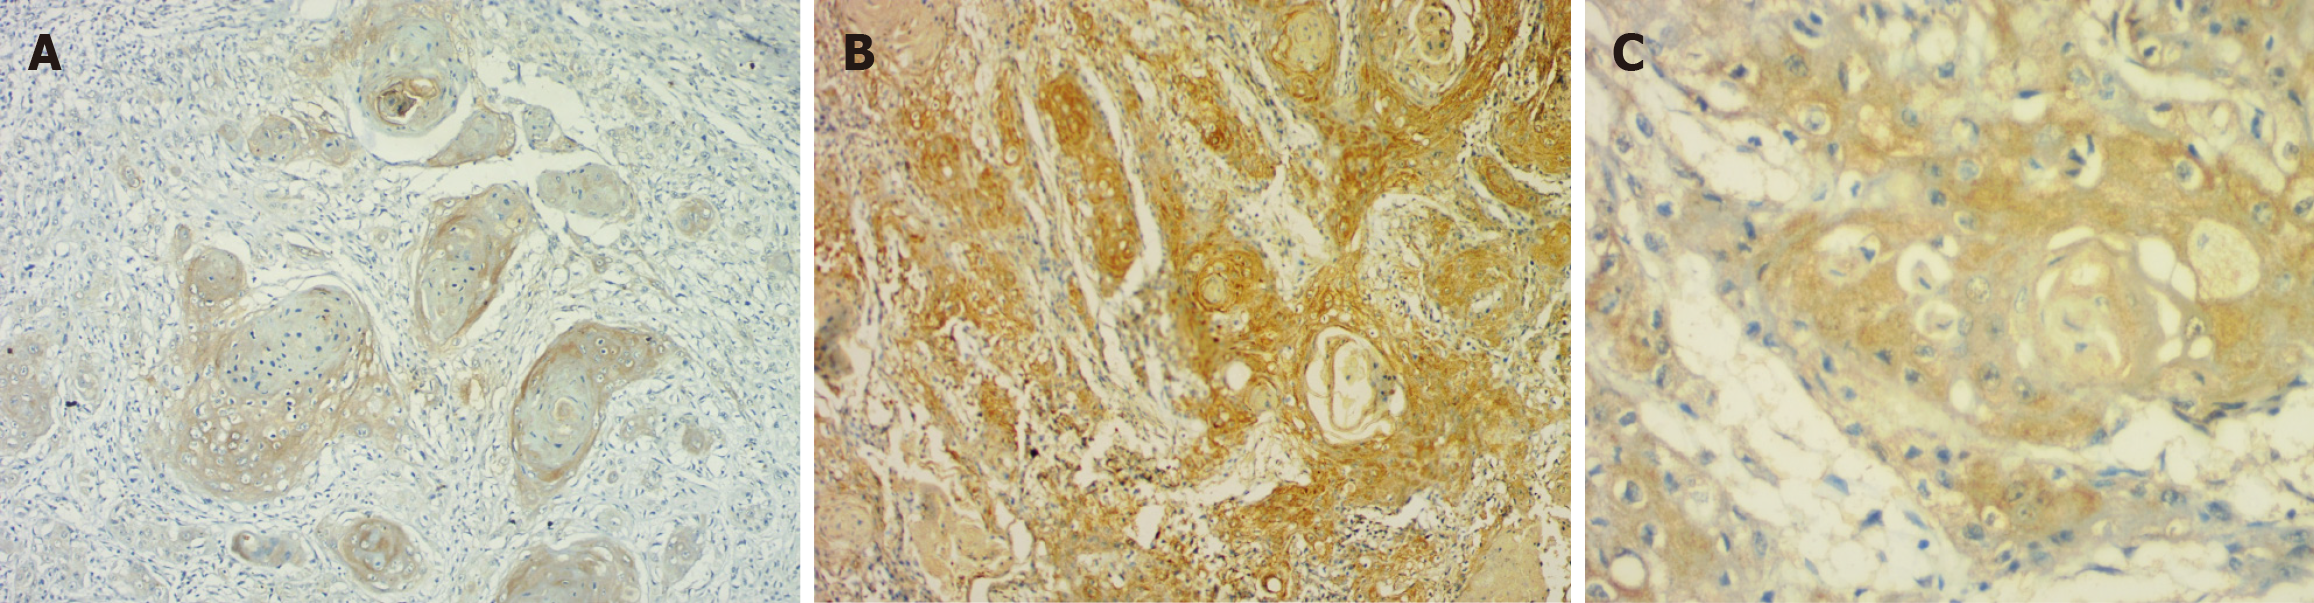

Intensity: The majority of cases (n = 28) in OED showed intense staining. However, in OSCC, only 11 cases showed intense staining, while the rest (n = 18) showed mild expression. A progressive reduction in intensity of stromal expression from OED to OSCC was evident (P = 0.0038).

Percentage: Twenty-three OED instances had > 50% positivity, six had 25%-50% positivity, and one had 1%-25%. However, in OSCC, the majority (20 cases) had decreased expression (1%-25% positive), while only 5 cases had > 50% and 4 cases had 25%-50%. A significant difference in the percentage of positivity was seen, with maximum stromal expression observed in OED and a marked reduction seen in OSCC (P = 0.0001) (Table 3, Figure 3).

ZEB1 expression in the stroma is analogous to that of immune cells and/or a specific subgroup of fibroblasts. In comparison to OSCC, ZEB1 stromal expression was greater in OED in terms of both intensity and positive percentage. It is unknown what the real cause or process is. The most plausible theory is that it controls the differentiation of stromal fibroblasts. ZEB1 in stromal carcinoma-associated fibroblasts (CAFs), leads to enhanced production and secretion of several paracrine signaling molecules into the surrounding stroma, such as fibroblast growth factor 2, fibroblast growth factor 7, vascular endothelial growth factor A, and interleukin 6.

It has been demonstrated that these paracrine signaling molecules, which are produced from stromal CAFs, bind to certain receptors on the tumor epithelial cells and activate p53, resulting in increased tumor growth and accelerated metastatic development in a variety of cancer types. Therefore, the ZEB1/p53 axis is a crucial stroma-specific signaling route that predisposes to carcinogenesis, and ZEB1 may act as an upstream regulator of p53 in stromal CAF.

The stromal cells with ZEB1 positivity have been reported in colon, bladder, breast, and lung carcinomas[37,38]. It has been hypothesized that ZEB1-dependent paracrine signaling from the stroma may influence E-cadherin regulation in tumor regions. Moreover, ZEB1 may predispose to EMT-associated carcinogenesis due to its role as a transcriptional repressor that negatively regulates E-cadherin expression, as evidenced in OSCC[38,39]. The existence of ZEB1-positive stromal cells implies that ZEB1 is significantly involved in carcinogenesis; nevertheless, the exact mechanism underlying ZEB1 expression in the stroma remains undisclosed.